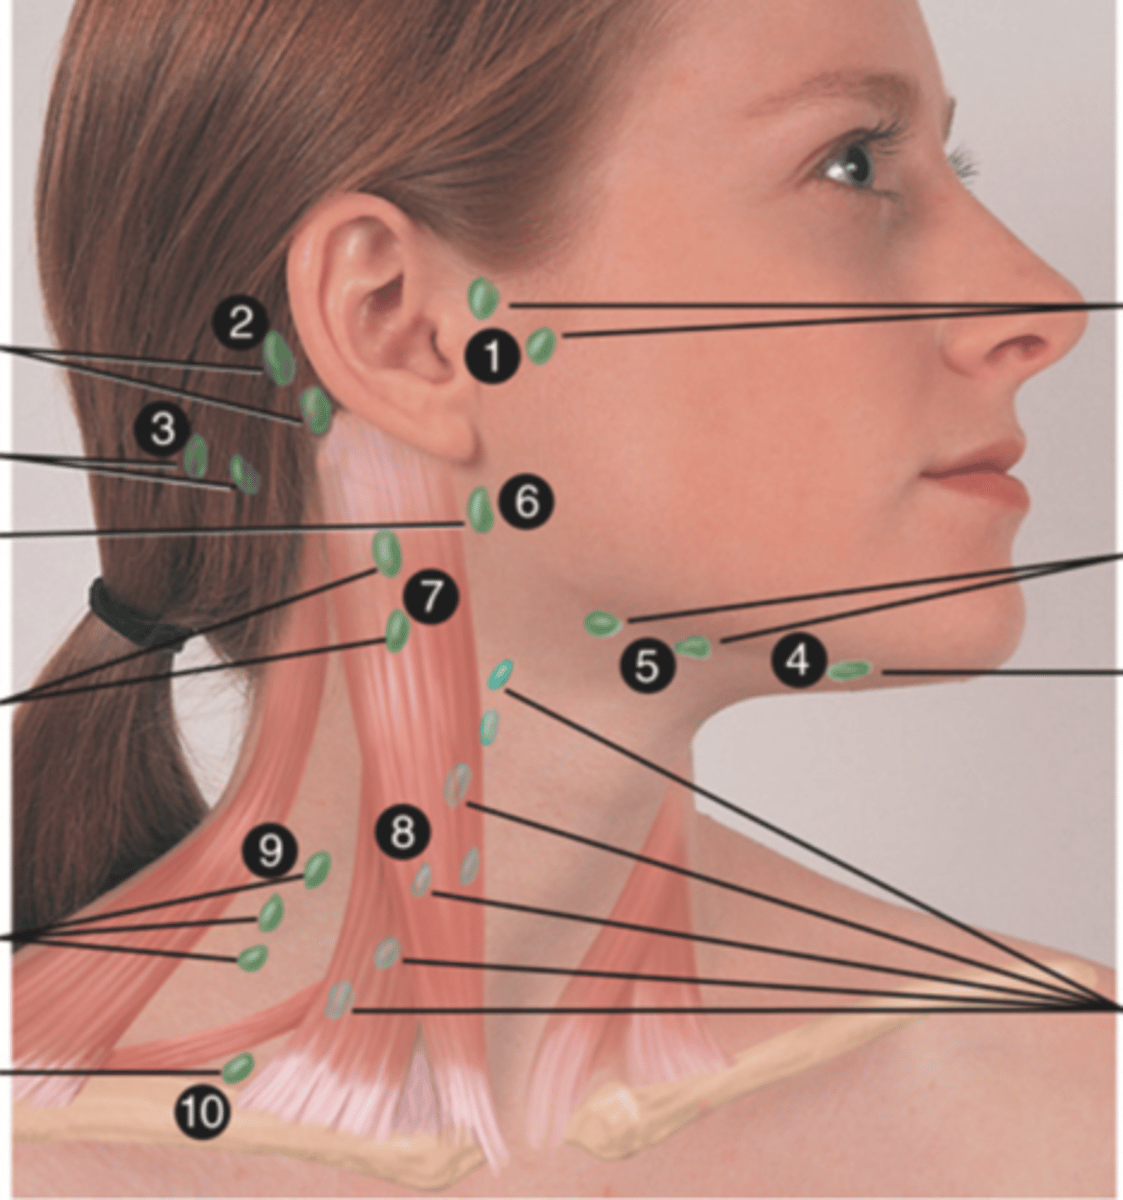

Major Lymph Nodes in the Neck (FUN!)

(Party People Often Sell Sardines Just So Dogs Pee Silver)

Preauricular Lymph Node

Lymph node in front of the ear (1)

Posterior Auricular Lymph Node

Lymph node behind the ear (2)

Occipital Lymph Node

Lymph node at the base of skull (3)

Submental Lymph Node

Lymph node under the chin (4)

Submandibular Lymph Node

Lymph node along base of mandible (5)

Jugulodigastric (Tonsil) Lymph Node

Lymph node under the angle of the mandible (6)

Superficial Cervical Lymph Node

Lymph node overlying the sternomastoid muscle (7); can feel enlarged even when there are no problems

Deep Cervical Chain Lymph Node

Lymph node located on the posterior triangle of the neck (8)

Posterior Cervical Lymph Node

Lymph node in the posterior triangle along the edge of the trapezius muscle (9)

Supraclavicular Lymph Node

Lymph node just above and behind the clavicle, at the sternomastoid muscle (10)